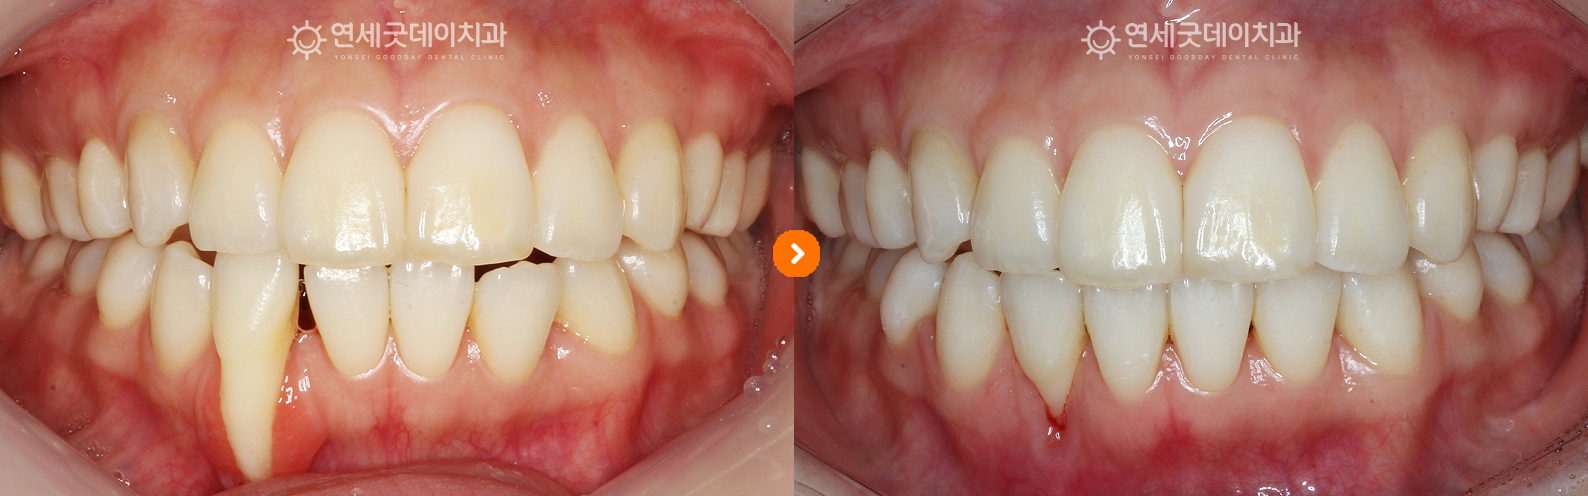

▲ 아랫니 부분교정 완료 (촬영시기 : 2025년 8월)

약 10개월 간의 치주교정 치료가 종결되었으며,

▲ 치주교정 치료전후 비교 (촬영시기 : 2024년 10월 / 2025년 8월)